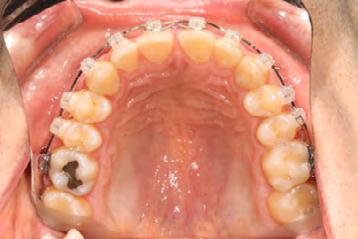

Palatal mini-implants were placed by a periodontist, followed by placement of the rapid palatal expander (RPE) and bonding of the mandibular arch with self-ligating Damon clear braces. Patient had SARPE surgery performed by the oral surgeon three weeks later (Figure 2), and the expander was turned once a day for three weeks (Figure 3). The maxillary arch was then bonded. Both archwires were incremen-

Figure 1. Initial records.

tally upgraded to an 18 x 25 NiTi wire, and the patient was placed on vertical elastics on the right side. With enough space for the tongue, the lateral open bite began to close.